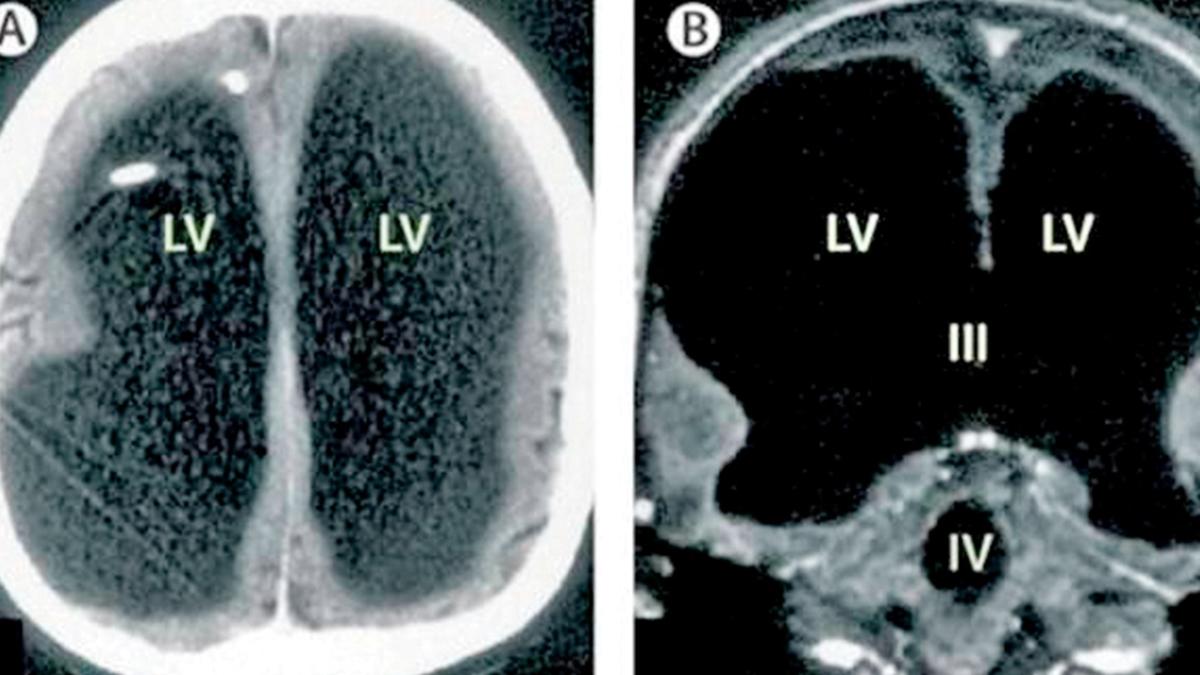

Fransa'da 44 yaşındaki adam, bacağında ağrı ve güçsüzlük hissedince doktora gitti. Tarama sonrası adamın beyninin yarısının olmadığı, 'Hidrosefali' adı verilen kafatasında sıvı bulunduğu ortaya çıktı. Bilişsel psikolog Axel Cleeremans, adamın normal bir yaşam sürdüğünü açıkladı.

Şikayeti sırasında yapılan IQ testinin sonucu 84 olarak belirlendi; bu, normal aralığın biraz altında. Doktorlar, hastalığının nedeninin beyninde biriken sıvı olduğunu ve bu durumun 30 yıl boyunca beyninin büyük kısmının tahrip olmasına yol açtığını düşünüyor.